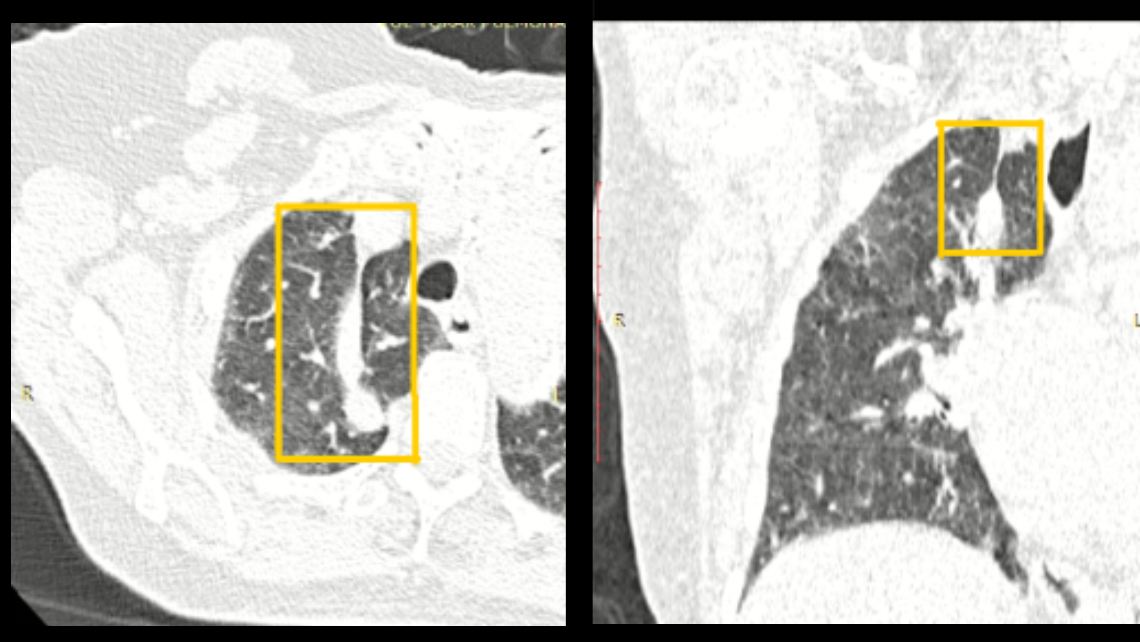

Se observan en el estudio tomográfico de tórax hallazgos radiológicos compatibles con neumopatia viral por COVID-19, cardiomegalia y además se evidencia; lóbulo y cisura accesoria en el LSD, en relación a cisura y lóbulo accesorio de la vena ácigos.

La cisura accesoria para el lóbulo de la vena ácigos se presenta en 0,2 a 1,2% de los pacientes, durante el desarrollo embrionario la vena ácigos queda normalmente sobre el bronquio principal derecho. En esta variante anatómica ocasionalmente no ocurre así y el cayado de ácigos queda sobre el vértice pulmonar, de modo que, al crecer el pulmón, la vena ácigos arrastra un pliegue de la pleura formando un lóbulo accesorio en el pulmón derecho que está situado medialmente a esta fisura anormal.

Está compuesta por cuatro capas pleurales, dos viscerales y dos parietales y representa la invaginación de la pleura apical derecha por el trayecto de la vena ácigos (meso-ácigos), desde la región paravertebral hasta el ángulo tráqueo-bronquial derecho y de esta manera, delimita el lóbulo ácigos, que se sitúa medial al lóbulo superior y superior al hilio del pulmón derecho. Con mayor frecuencia recibe ramificación bronquial de las ramas anterior y apical del bronquio para el segmento apical del lóbulo superior derecho.

El lóbulo de la ácigos es una variación anatómica normal y se trata de un hallazgo radiológico sin repercusión clínica que podemos observar en la radiografía convencional de tórax y de mejor manera en el estudio tomografico.